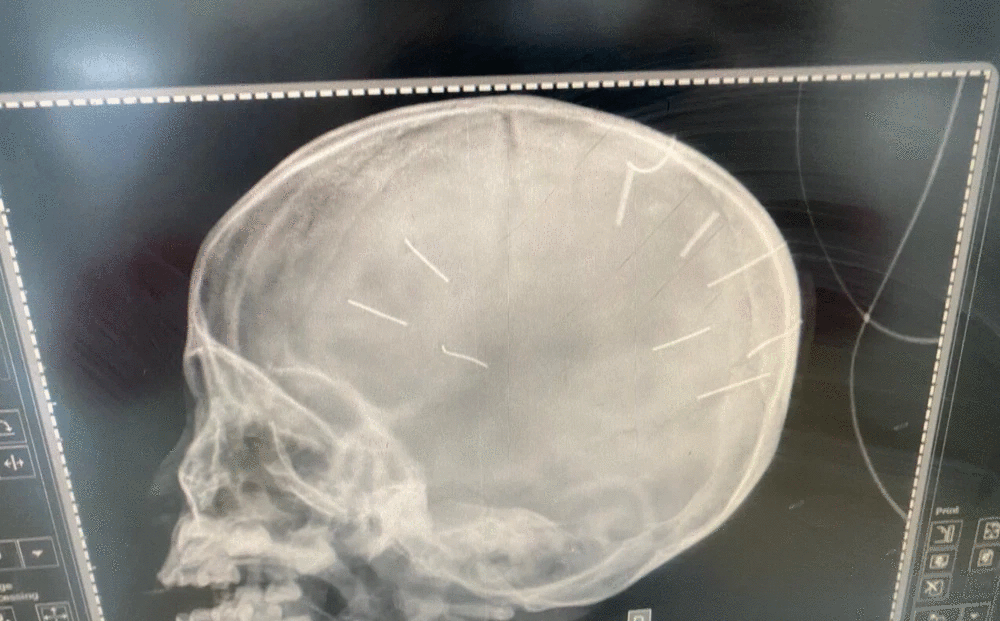

HÌnh chụp X-quang của bé A.

Liên quan đến vụ việc bé Đ.NA. (3 tuổi, trú tại xã Canh Nậu, huyện Thạch Thất, Hà Nội) bị 9 chiếc đinh ghim vào đầu, hiện tại bé đang trong tình trạng rất nguy kịch, đang được các y bác sĩ BV Xanh Pôn nỗ lực cứu chữa.